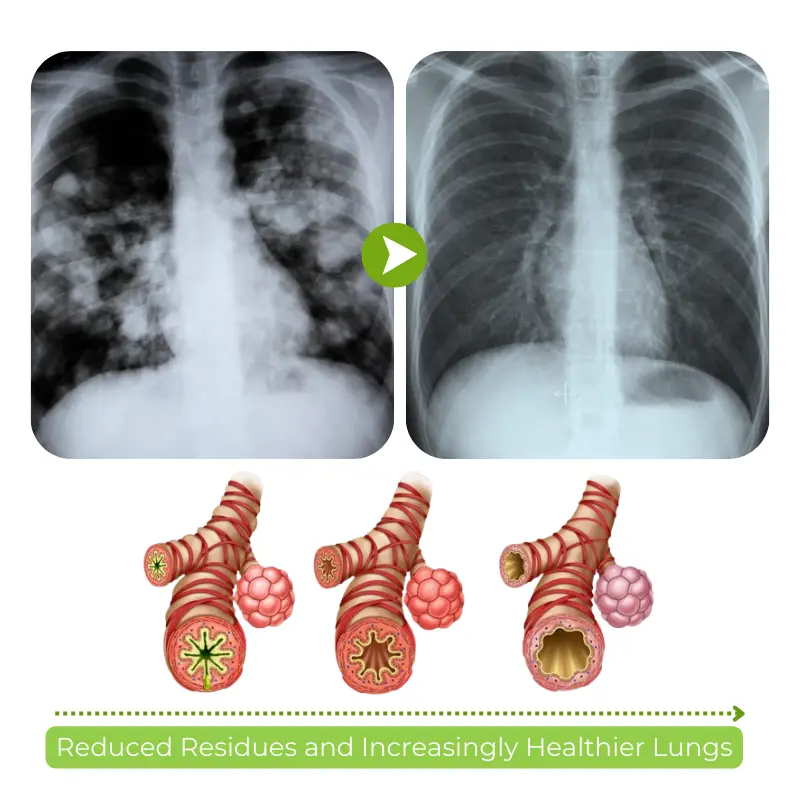

- Detox and Revitalize – Remove harmful toxins caused by smoking, pollution, and environmental factors. This deep detoxification process supports the regeneration of healthy lung tissue, promoting stronger and cleaner lungs over time.

Guarantee No. 2: Proven Effectiveness – Biancat® RespiCleanse isn’t just a promise—it’s a commitment to measurable results. You can expect noticeable improvements in your lung health, with enhanced breathing, reduced irritation, and a cleaner respiratory system. But it doesn’t stop there.